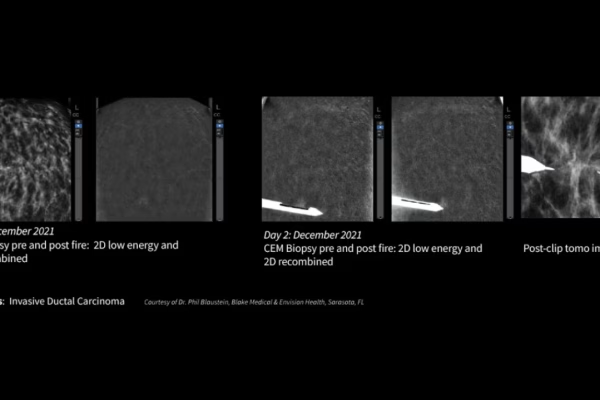

Mammographie GE Senographe